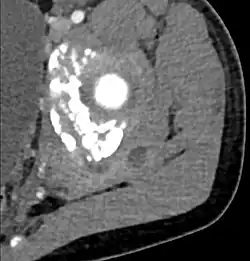

Diagnostic methodDiagnostic method used for PM includes ultrasound, CT scan and MRI. Ultrasound can be helpful in showing muscular heterogeneity or a purulent collection but it is not useful during the first stage of the disease. CT scan can confirm the diagnosis before abscesses occur with enlargement of the involved muscles and hypodensity when abscess is present, terogenous attenuation and fluid collection with rim enhancement can be found. MRI is useful to assess PM and determine its localization and extension